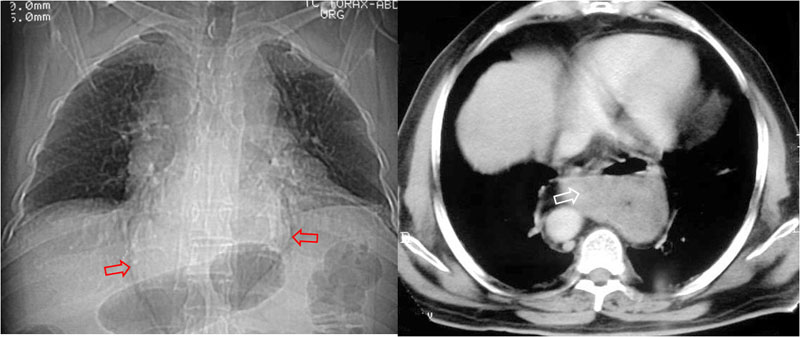

SIGNO TORACOABDOMINAL o DEL ICEBERG

Signo de utilidad para determinar la localización de una masa en la encrucijada toracoabdominal. Si la masa está bien definida y tiene bordes convergentes en forma de paréntesis –como en la imagen-, a ambos lados de la columna, es torácica, porque queda dibujada por el aire que la rodea. Por el contrario, cuando los bordes son divergentes, suele tratarse de masas abdominales (adenopatías, aneurismas).

SIGNO DE LOS CUATRO VASOS

En la TC de tórax normal, las cuatro arterias supraaórticas (ambas carótidas y ambas subclavias) sólo se ven en los cortes más craneales del mediastino, cuando se ha dividido el tronco braquiocefálico derecho. Por ello, cuando se ven los cuatro vasos inmediatamente por encima del cayado, suele existir alguna anomalía vascular mediastínica, normalmente con afectación del cayado.

En la imagen vemos los cuatro vasos (flechas) en un plano inmediatamente por encima del cayado aórtico.

Un corte en un plano inmediatamente inferior al anterior, a la altura del cayado, muestra la anomalía que causa el signo: la disposición a la derecha del arco aórtico.